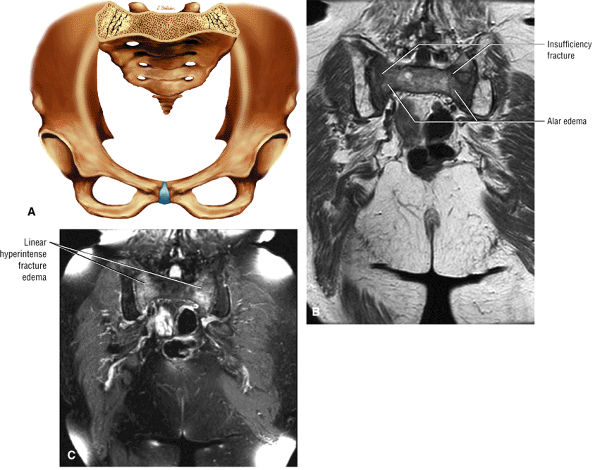

FIGURE 3.28 ● Normal coronal anatomy of the hip. (A, B) In the setting of pubic rami fractures, the sacrum and sacroiliac joints should be examined for the presence of fractures or a diastasis completing the pelvic ring fracture. (C, D) Sacral insufficiency fractures or sacroiliitis is seen only on images with a large field of view. Occasionally they are the only significant finding in a patient with unilateral hip pain. (E, F) Images with a large field of view should also be used to examine the pelvic viscera, especially in women, for adenopathy, masses, and adnexal or uterine pathology. (G, H) Articular cartilage covering the acetabulum and femoral head is clearly displayed. A small portion of the medial femoral head (the fovea) and a large portion of the medial acetabulum (the acetabular fossa) are devoid of cartilage. (I, J) Early signs of degenerative arthrosis may be seen in the anterior superior quadrant of the hip, including cartilage thinning and fraying, subchondral edema in the anterosuperior acetabulum, and anterosuperior labral tearing. (K, L) The anterior superior portions of the bilateral acetabuli are visualized on images obtained with a large field of view. These images allow appreciation of subtle differences in symmetry of the acetabular contour. Even mild acetabular dysplasia may be accompanied by unilateral labral tears and chondral degeneration. (M, N) Osseous spurring at the symphysis pubis is a common finding. Occasionally, acute or insufficiency fractures occur immediately to the left or right of the symphysis pubis, and are seen only on images obtained with a large field of view.